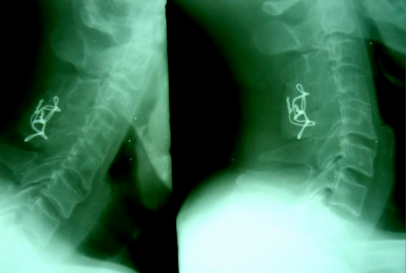

SAU MỔ: C5-C6 đã được nắn chỉnh. KHX Bohlman cải tiến.

THẲNG NGHIÊNG

SAU MỔ 4 THÁNG: tình trạng KHX vẫn tốt, không di lệch thứ phát, không giãn chỉ, không đứt chỉ.